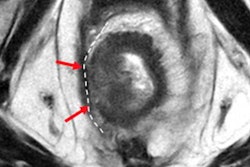

Another study to be presented at RSNA (SSA07-04) looks at tumor heterogeneity in MRI as a potential prognostic biomarker in patients with rectal cancer who have undergone chemoradiotherapy.

A third RSNA presentation by Ganeshan and colleagues (SSA07-06) looks at the performance of texture analysis, diffusion-weighted imaging (DWI), and perfusion imaging in predicting treatment response in rectal cancer patients studied with 3-tesla MRI.

The underlying principle is the same for CT and MRI analysis: It's simply a matter of tuning the software to Hounsfield Units or signal intensity. The software technique approach starts with a filtration histogram analysis; the second step is quantification. The filtration extracts features of different sizes and variations in intensity from the tumor, enhancing and quantifying these features, he explained.

TexRad breaks down tumor images into different components separately -- fine structures separately, medium structures separately, and the large coarser structures separately, and it breaks down the images and quantifies the different distributions or patterns via the histogram analysis.